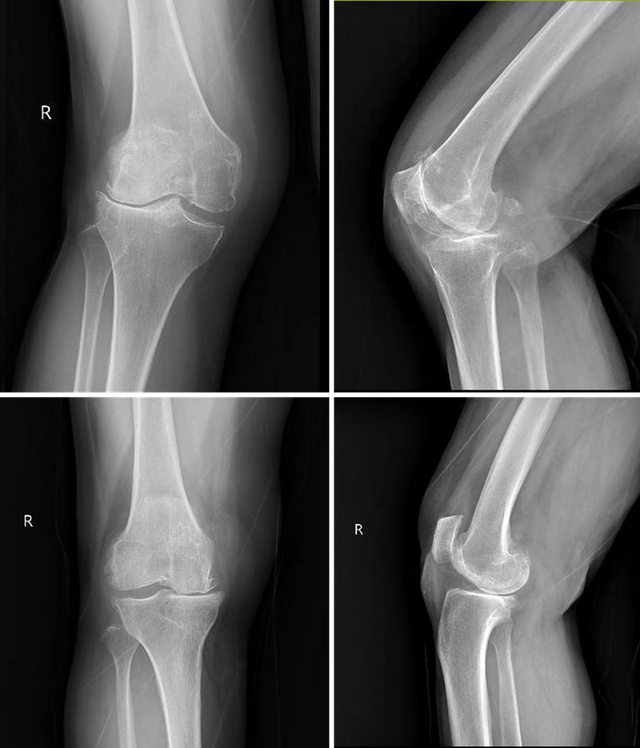

两位年过七旬的阿姨膝骨关节炎已伴随她们几十年,分别出现了膝关节严重的外翻与内翻畸形,上下楼梯钻心的疼、走几步路就得歇、连日常下蹲都成了“奢望”。随着病情加重,关节畸形、活动受限彻底打乱了她们的生活节奏,“能好好走两步”成了她最迫切的心愿。

手术当日,手术室的高清屏幕上,两位阿姨膝关节的3D建模数据清晰呈现:从截骨角度到平衡屈伸间隙,从假体型号到安装位置,每一项参数都经过术前精准测算。将术前畸形的膝关节通过机器人准确截骨完美地实现了内外侧间隙在屈伸过程中的平衡。